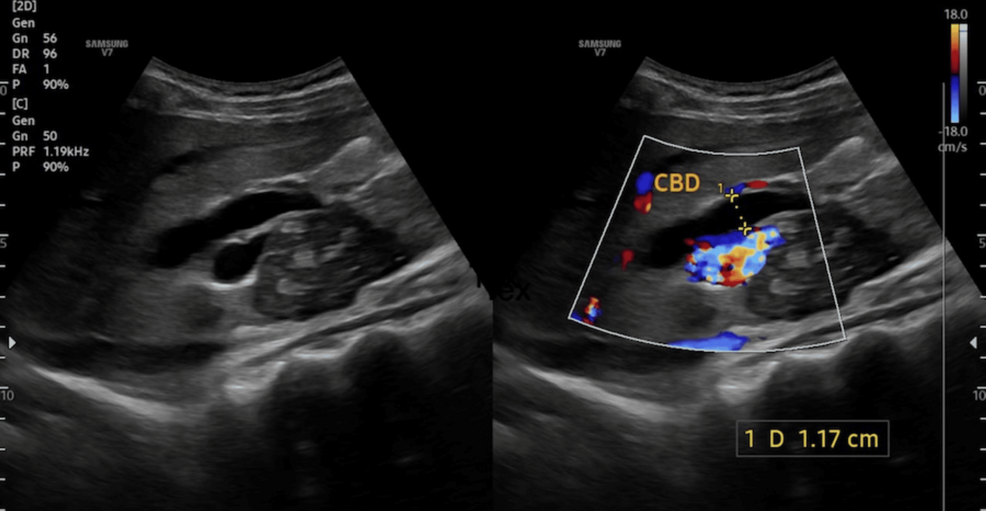

Obstructive Jaundice Due to Periportal Tuberculous Lymphadenopathy in a Patient With Multidrug-Resistant (MDR) Tuberculosis: A Case Report Cureus

Obstructive Jaundice Due to Periportal Tuberculous Lymphadenopathy in a Patient With Multidrug-Resistant (MDR) Tuberculosis: A Case Report – Cureus